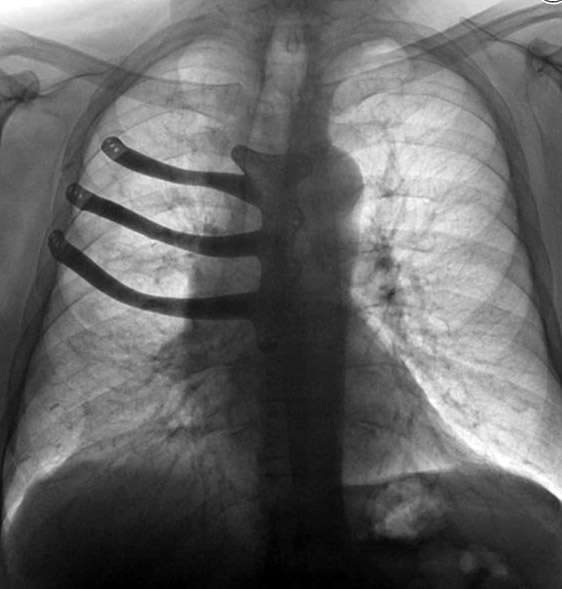

Врачи госпиталя Моррисон в британском городе Суонси реконструировали с помощью 3D-принтера грудную клетку своего пациента. 71-летнему Питеру Мэггзу из-за раковой опухоли пришлось удалить половину грудной кости и три ребра, сообщает ABMU Health Board.

Как правило, в таких случаях хирурги отливают протез из медицинского цемента во время операции, но технология 3D-печати позволила изготовить имплант из титанового сплава и сократить время операции на два часа. При изготовлении протеза использовалась компьютерная томография грудной клетки Мэггза. Это один из первых случаев печати подобных протезов в Британии.

Операция длилась восемь часов. По словам врачей, имплант сел идеально, и они планируют практиковать такое протезирование и в будущем.